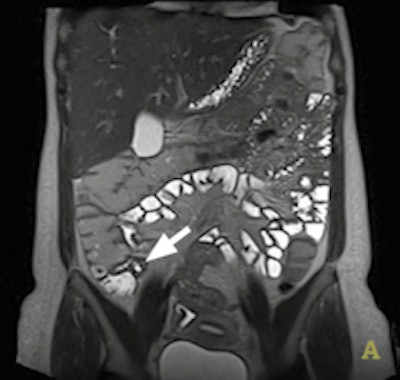

The application of DWI is well-established in helping to detect and characterize disease in the brain and liver, but it is relatively new in Crohn's disease. Key to management of this chronic relapsing disease of the bowel is differentiating between active inflammatory disease and chronic fibrosis because this helps determine whether the patient will be treated with immunosuppressive drugs or surgical resection.

Dr. Stuart Taylor from London.Gastrointestinal imaging specialists believe there is compelling evidence that bowel affected by Crohn's disease leads to abnormal DWI,and there is considerable interest in whether DWI can help aid both detection of affected bowel and differentiation of active disease from fibrosis, according to Dr. Stuart Taylor, consultant gastrointestinal radiologist and professor of medical imaging at University College London. He is concerned about how the inflammatory process affects the movement of water, yielding abnormal DWI signal.

However, recent information correlating MRI with histopathological examination of surgical resection specimens suggests chronic fibrosis could affect DWI signal in a similar way as inflammation. This means that when there is a question about fibrosis, for example in longstanding disease or in patients who are still symptomatic after long drug treatments, DWI probably should not be used on its own for differentiation. Instead, the radiologist should deploy conventional T2 and contrast-enhanced sequences which can help differentiate active versus nonactive disease.

He envisages that high sensitivity of DWI for abnormal bowel will give it a role in initial staging of the small bowel in newly diagnosed patients. It will also be useful in established Crohn's disease cases for defining how active the disease is, and particularly for monitoring therapy response during treatment. Taylor reports particular use of DWI by pediatric radiologists as a sensitive, minimally invasive method to identify abnormal bowel in young children. In addition, DWI may replace sequences using intravenous contrast, particularly if detection of fibrosis is not the main clinical question.